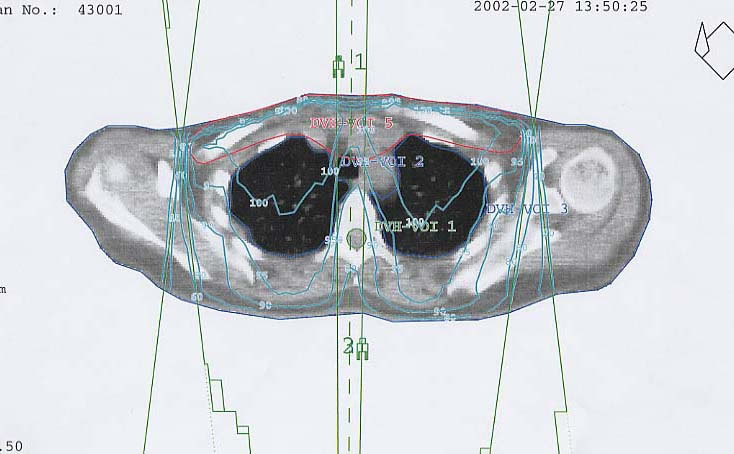

Schilddrüsenkarzinom: Bestrahlungsplan